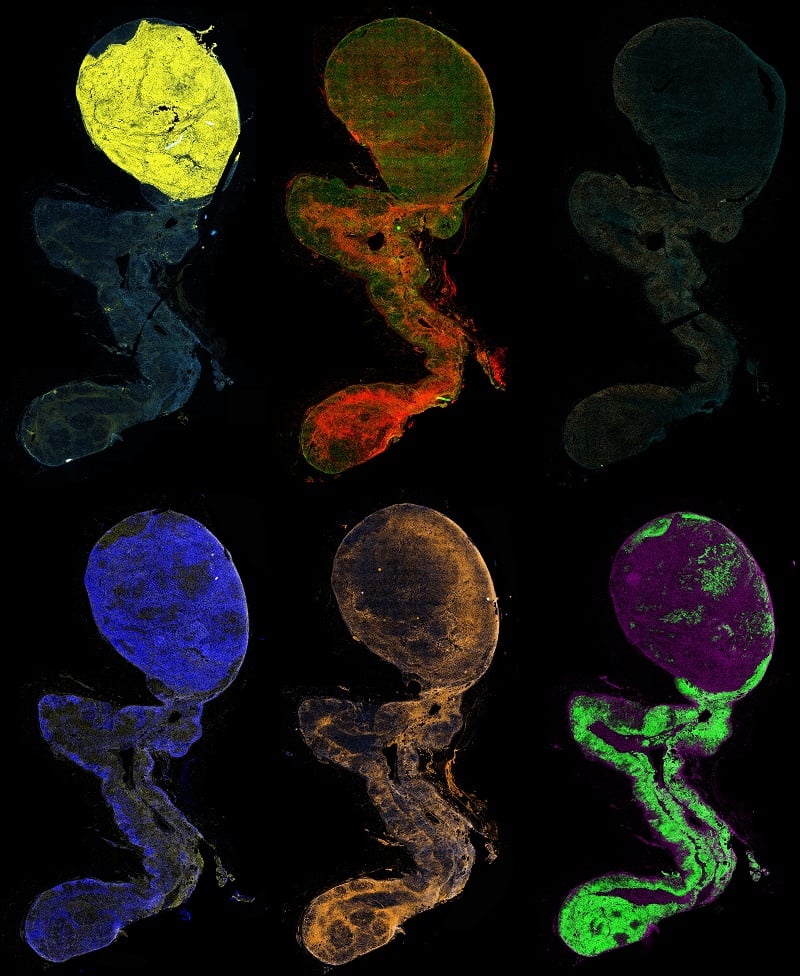

Indrajit Chowdhury, Saswati Banerjee, Wei Xu, and Winston E. Thompson  Morehouse School of Medicine, Atlanta, Ga.

Endometriosis is an estrogen-dependent chronic gynecological inflammatory disorder. The immune system dysregulation may play a vital role in the initiation and progression of the disease. It has defined as the growth of endometrial tissue (specifically glands and stroma) outside the uterine cavity, predominantly in the peritoneal compartment. The knowledge of molecular and cellular regulation of the endometriotic endometrium is poor, mainly due to multiple autocrine-paracrine hormonal signaling and lack of study models that are reliable and reproducible. Moreover, 2D cell cultures do not truly represent 3D organ biology and functioning. Therefore, we established a rat epithelial cell-derived organoid culture system that recapitulates the epithelial layer of the endometrium. Representative phase images of rat uterine organoids were grown in Matrigel for a different duration. Also they develop placental villi like structures. Organoid stain with DAPI (Blue color).